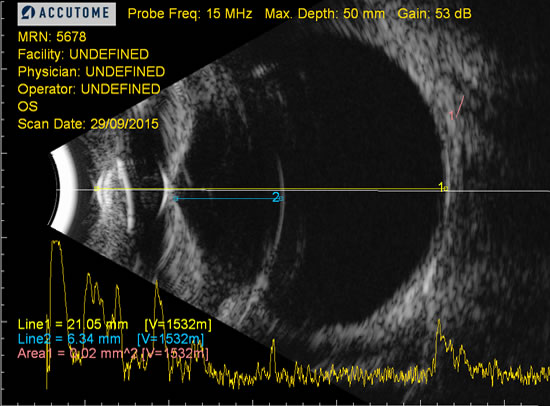

En medicina veterinaria, nuestros pacientes pocas veces presentan síntomas a no ser que la patología esté desencadenando estadíos fínales. Es en este momento cuando nos encontramos opacidades: edema corneal, endotelitis, turbiedad de humor acuoso por uveítis, cataratas, etc que impiden visualizar los componentes del ojo. La oftalmoscopia pasa a un segundo plano, recurriendo al ultrasonido.

En la actualidad se considera la modalidad de imagen como elección en el diagnóstico y control de las enfermedades oculares.